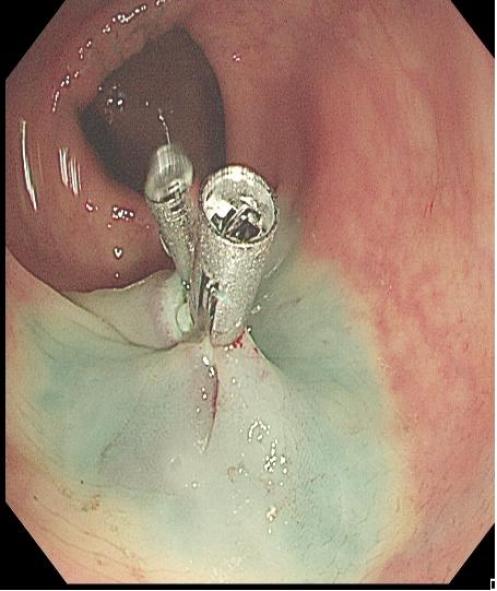

上下滑动查看△图5 大型病变的ESD治疗。